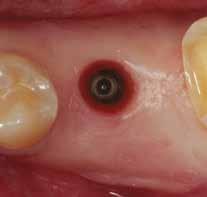

A fogpótlás készítésének lépései

Hathetes gyógyulás után a lágyszövetek kiválóan gyógyultak, és minden implantátum megfelelően osszeointegrálódott, amelyet a radiológiai vizsgálat is megerősítetett (9. és 10. ábra).

10. ábra: Lágyszövetek a hat hét gyógyulást követően.